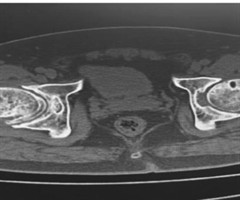

基于“行气一体,阴阳同调”理论治疗早期非创伤性股骨头坏死临床经验擷英

【摘要】王海东教授将传统经筋理论与现代解剖学知识相融合,以“行气一体,阴阳同调”为核心理念,运用针刀解结术治疗早期非创伤性股骨头坏死(NONFH),形成了独具特色的诊疗体系。王教授认为早期NONFH属“骨痹”范畴,其核心病机在于“筋伤骨损,...